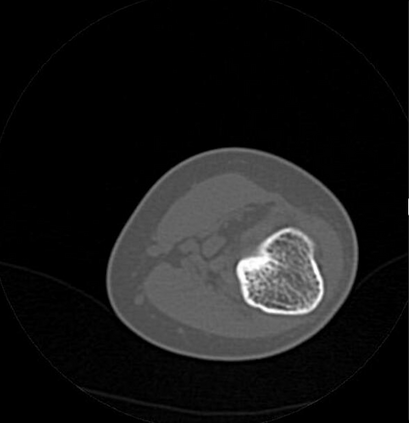

In this study, we aim to initiate the development of Radiology Foundation Model, termed as RadFM.We consider the construction of foundational models from the perspectives of data, model design, and evaluation thoroughly. Our contribution can be concluded as follows: (i), we construct a large-scale Medical Multi-modal Dataset, MedMD, consisting of 16M 2D and 3D medical scans. To the best of our knowledge, this is the first multi-modal dataset containing 3D medical scans. (ii), We propose an architecture that enables visually conditioned generative pre-training, allowing for the integration of text input interleaved with 2D or 3D medical scans to generate response for diverse radiologic tasks. The model was initially pre-trained on MedMD and subsequently domain-specific fine-tuned on RadMD, a radiologic cleaned version of MedMD, containing 3M radiologic visual-language pairs. (iii), we propose a new evaluation benchmark that comprises five tasks, aiming to comprehensively assess the capability of foundation models in handling practical clinical problems. Our experimental results confirm that RadFM significantly outperforms existing multi-modal foundation models. The codes, data, and model checkpoint will all be made publicly available to promote further research and development in the field.